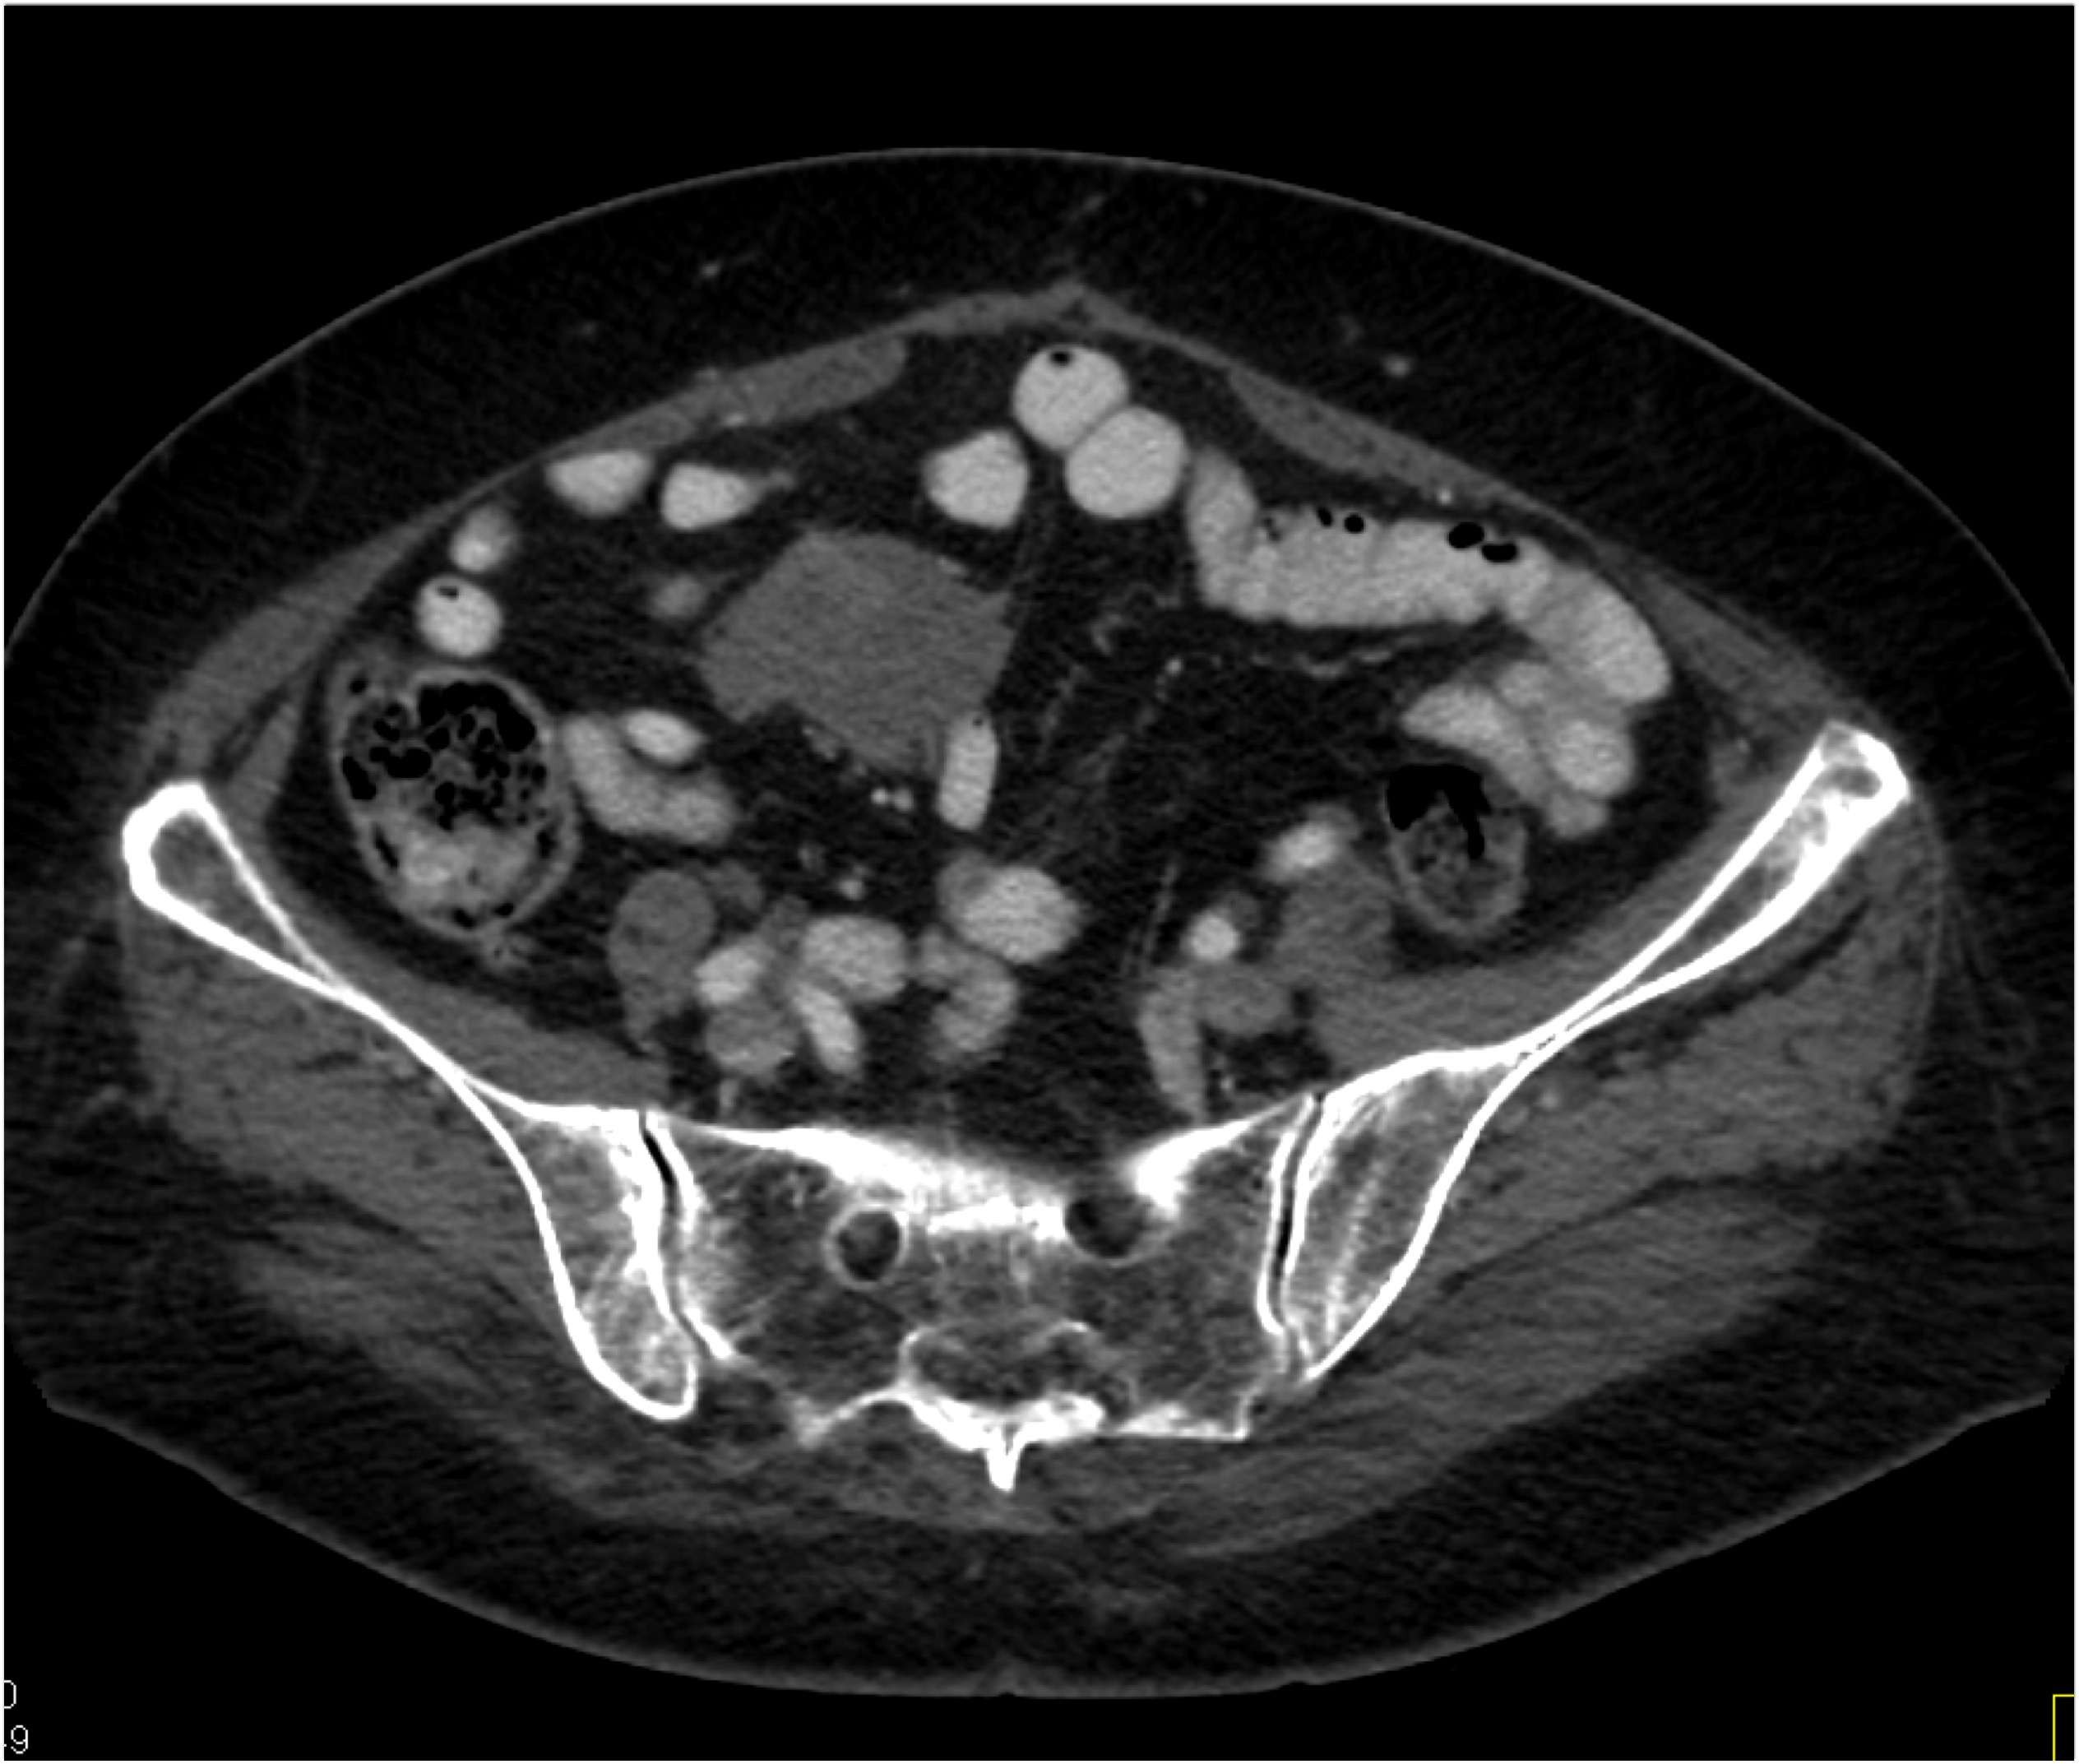

8) The most likely diagnosis in this case is?

clear cell renal cell carcinoma

large B-cell lymphoma

seminoma

renal abscess